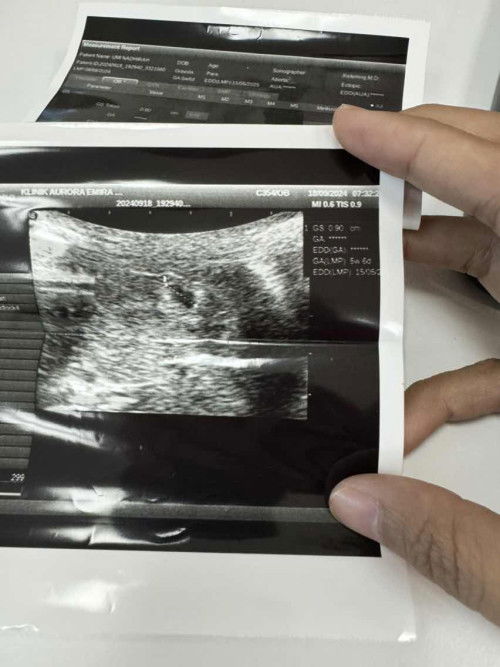

Kantung bentuk irregular

Ada sesiapa pernah experience irregular sac? #bantujawab #firstmom

Tgk shape dia kot. My SIL a sonographer. Dia ckp irregular. Tgk kantung dlm scan tu tak shape oval or bulat pun.